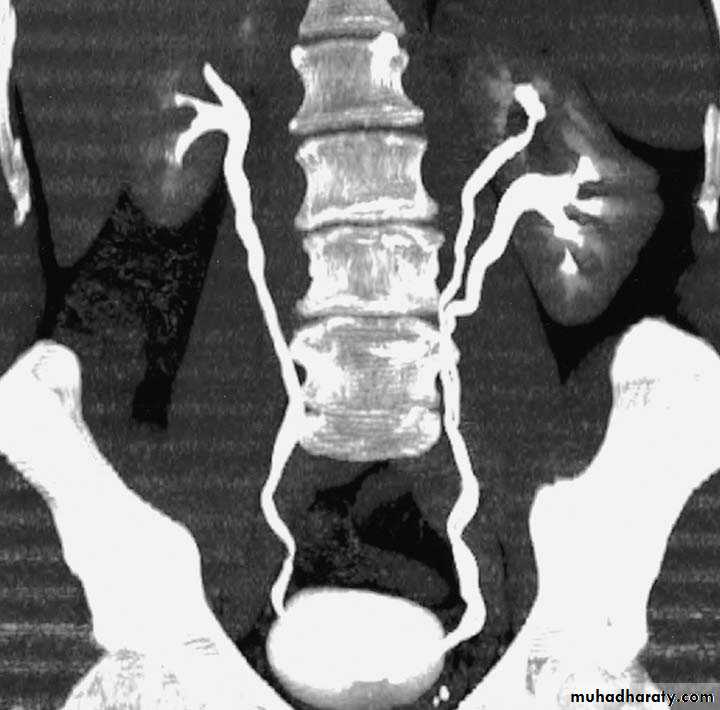

Ureteropelvic Junction (UPJ)(PUJ) Obstruction (stenosis)

The most common cause of significant dilation of the collecting system in the fetal kidney

Boys > Girls

Left-sided lesions predominate

15% bilateral

ETIOLOGY

Intraluminal : mucosal fold that causes valve

like effect.

Intrinsic (intramural) interruption in the

development of the circular musculature of the UPJ

Extrinsic An aberrant, accessory, or early-branching

DIAGNOSIS

U/S: hydronephrosis

IVU: diagnostic , hydronephrosis with

fixed stenotic segment or complete

obstruction

CT scan: hydronephrosis that ends

abruptly